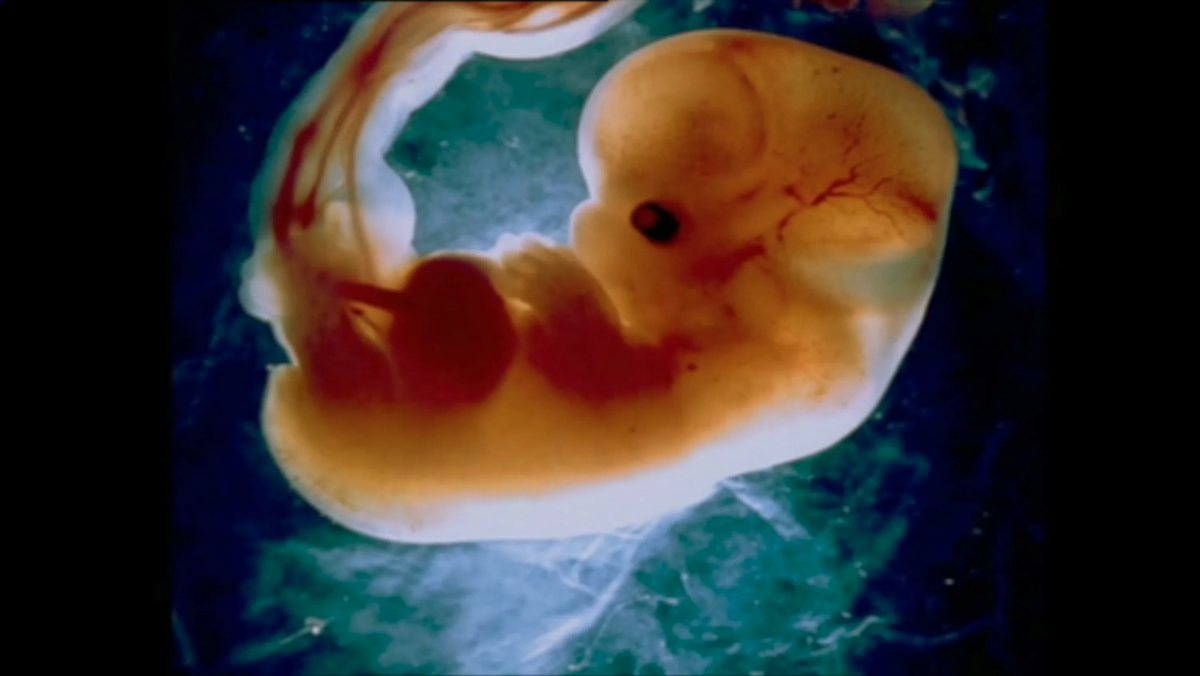

На шестой неделе беременности плодное яйцо увеличивается до 25 мм, а сам плод достигает размера около 6 мм. Это время, когда продолжается закладка органов и систем, и важным событием становится начало формирования головного мозга. Нервная система развивается с невероятной скоростью, и крошечное существо уже может реагировать на внешние раздражители.

В этот период закладываются зачатки ручек и ножек. Хотя они ещё очень маленькие и неразвиты, вскоре вы сможете с нежностью целовать эти сладкие ладошки и пяточки. Это время — начало движения крови по организму эмбриона, что является важным этапом в его развитии.

Одним из самых захватывающих событий на этом сроке является начало сердцебиения. Сердце крошечного плода бьётся в два раза чаще, чем у взрослого человека, и его частота составляет 140–150 ударов в минуту. Это свидетельствует о том, что малыш начинает активно развиваться и готовится к дальнейшему росту.

На шестой неделе продолжается закладка органов: формируются зачатки легких, костного мозга и селезенки. Наружные половые органы только начинают намечаться, и вскоре вы сможете узнать, будет ли у вас мальчик или девочка. В этот период также происходит дифференцировка пищеварительного тракта: кишечник уже имеет три петли, формируется пищевод, а в пищеварительной трубке появляется расширение — будущий желудок.